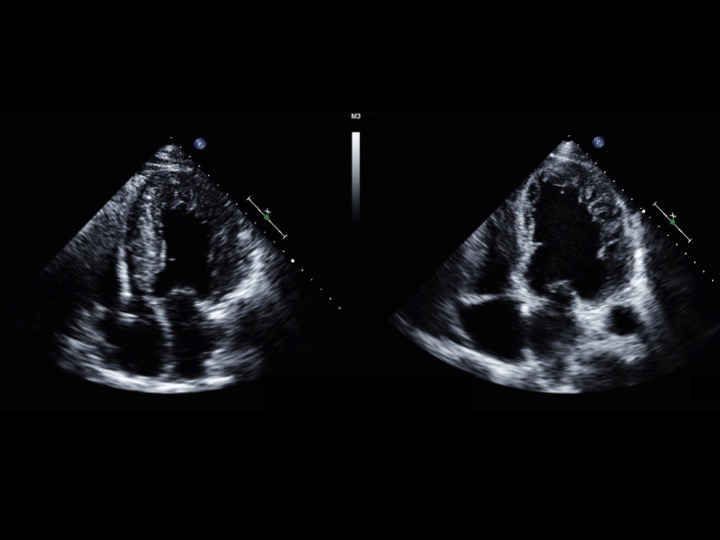

Case Presentation: A 60-year-old man with no comorbidities presented with multiple episodes of substernal chest pressure and reduced exercise tolerance. Cardiac catheterization was notable for severe systolic dysfunction with left ventricular dilatation without coronary disease. Echocardiography was significant for an ejection fraction (EF) of 20% with global hypokinesis and extensive left ventricular (LV) trabeculations consistentwith non-compaction. Repeat echocardiography after nine months of optimal medical therapy for systolic heart failure did not yield any significant change in EF, degree or depth of visible trabeculations, or LV cavity size (LV diameter, end diastole [LVIDd] 7.5cm, LV mass index 197 g/m 2 ). At this time, the patient met indications for cardiac resynchronization therapy (CRT), with QRS prolongation and presence of left bundle branch block (LBBB) morphology on his electrocardiogram (ECG), and underwent implantation of a biventricular ICD. On repeat visits, he improved clinically, with reported increased exercise tolerance. Echocardiography two years after initiation of CRT revealed an EF of 35%, decreased LV cavity size (LVIDd 5.3 cm, LV mass index 143 g/m 2 ), and notably decreased LV trabeculations.